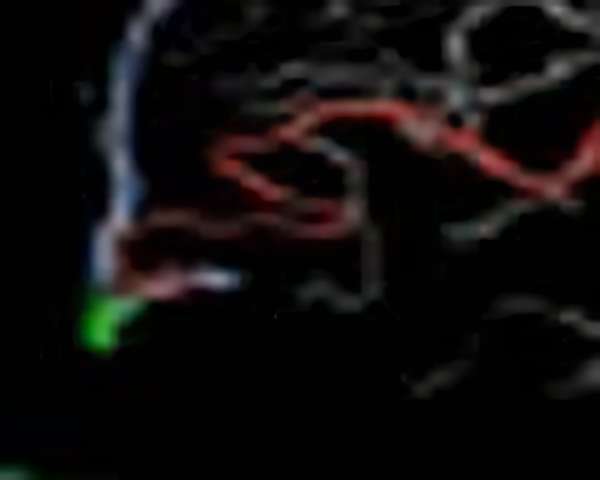

手術中